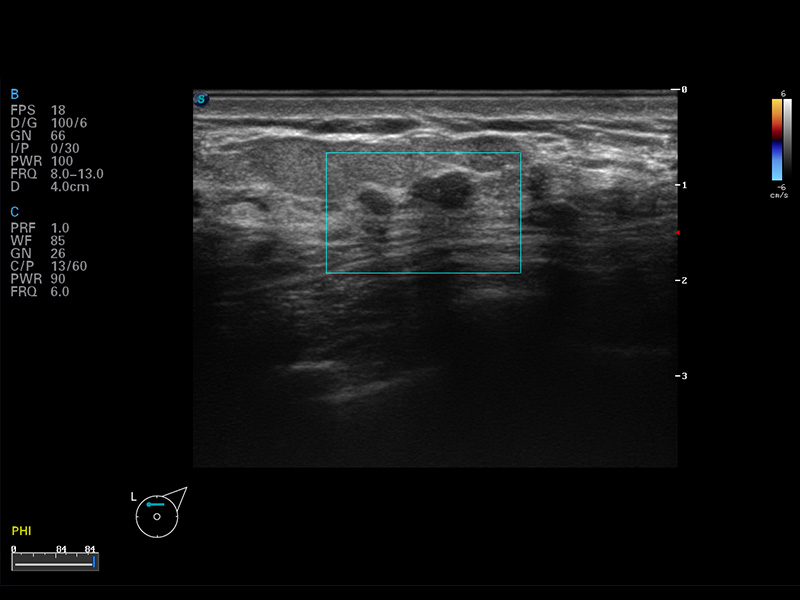

S8 EXP便携式彩色多普勒超声诊断仪是DB中国旗舰官方网站研发的高端全身应用型便携彩超。高通道的VIS平台融合可视化(Visual)、智能化(Intelligent)和人性化(Smart)的特点,配以DB中国旗舰官方网站自主研发生产的探头大家族,使您能够快速、准确的获得病人信息,提高工作效率的同时减轻疲劳。

μ-Scan微米成像

谐波成像

空间复合成像